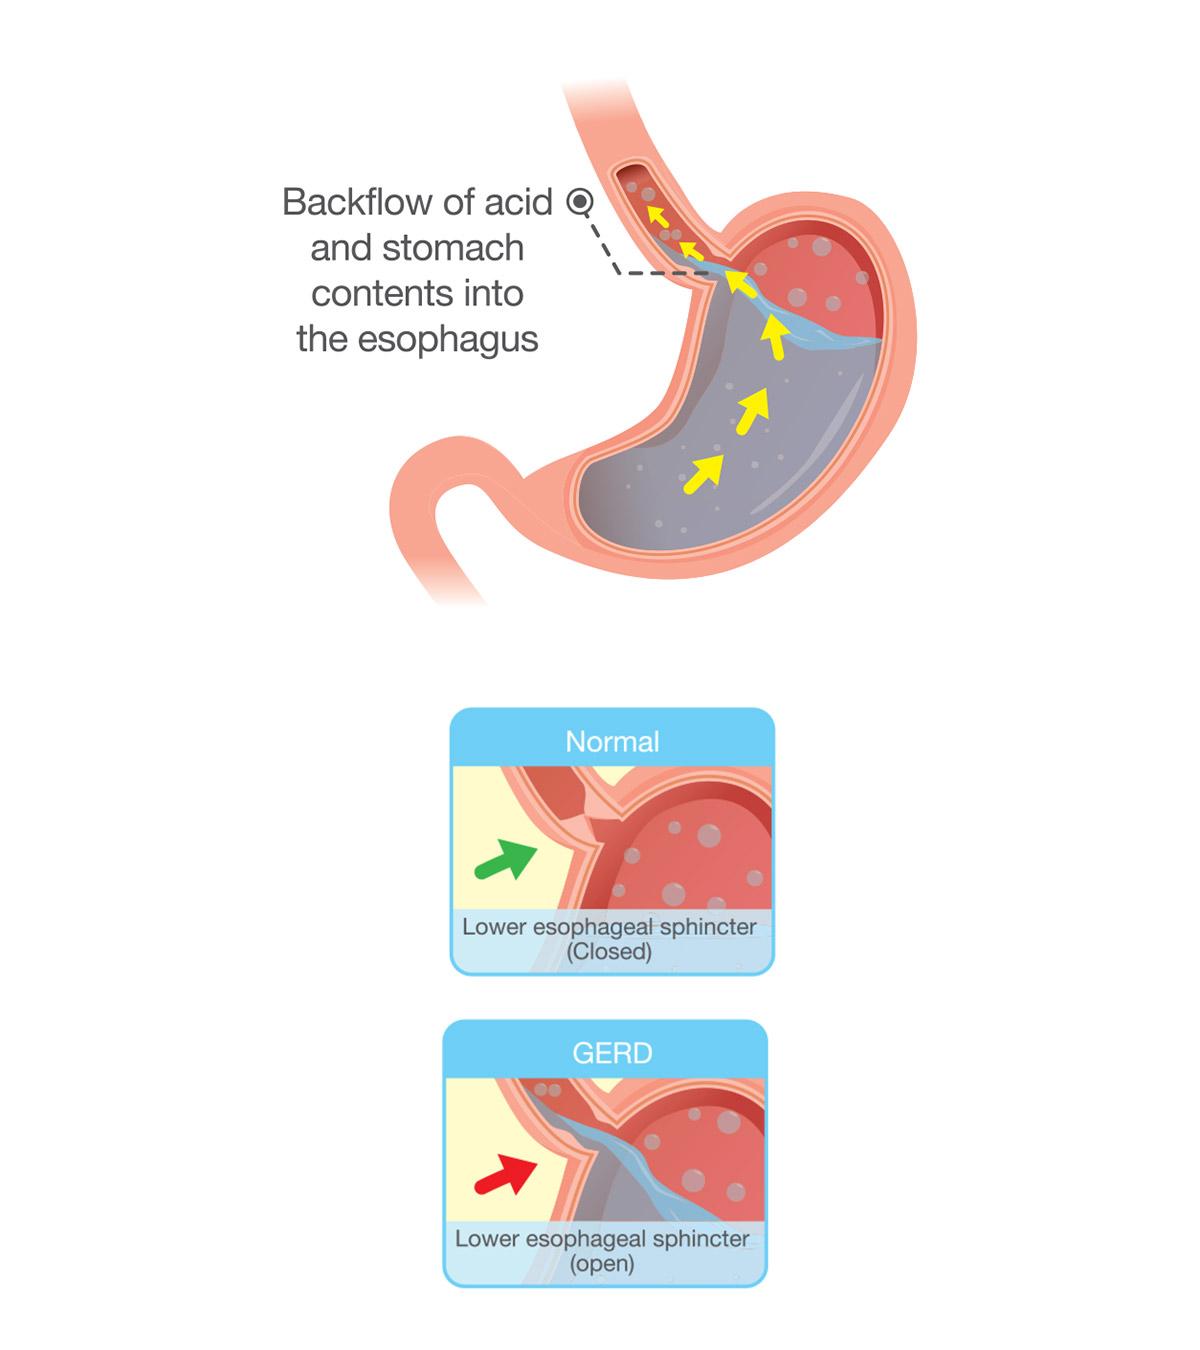

- During acid refluxiBackflow of digestive acid from the stomach through the esophagus, causing a burning sensation in the chest. , as it causes discomfort.